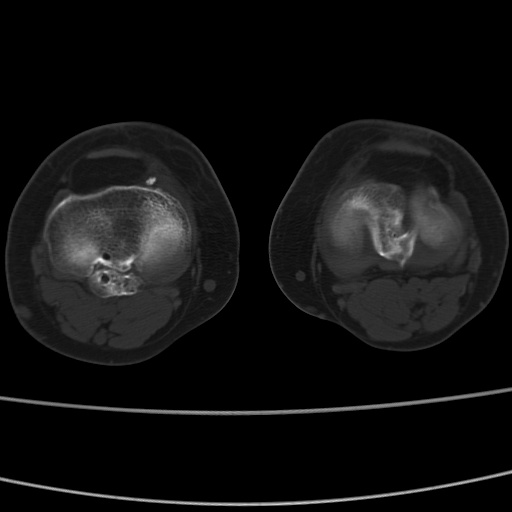

女性,50岁。【请提供患者临床症状体征】

右膝关节退行性改变,关节游离鼠。

右膝关节退行性改变,滑膜黏液囊钙/骨化并游离。

右膝关节退行性改变